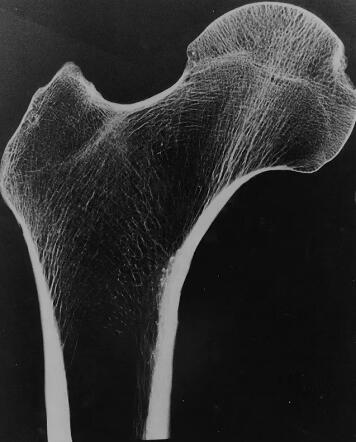

人體骨骼通過小梁的海綿狀結(jié)構(gòu)獲得耐用性,這種海綿狀結(jié)構(gòu)是由相互連接的垂直柱狀支撐和水平桿狀支撐作為柱和梁組成的網(wǎng)絡。小梁越密集骨骼在日常活動中就越有彈性,但是疾病和年齡會影響這種密度。

圖像顯示出相互連接的白線,這些線構(gòu)成了小梁結(jié)構(gòu)。來源:普渡大學

研究團隊指出,當人們衰老時他們的骨骼中首先失去的是水平支撐,這一狀況將增加骨骼在多個循環(huán)載荷作用下斷裂的可能性。研究團隊發(fā)現(xiàn),垂直的柱狀支撐結(jié)構(gòu)與骨骼的剛度、強度相關(guān),而水平的支撐結(jié)構(gòu)與骨骼疲勞壽命有關(guān)。